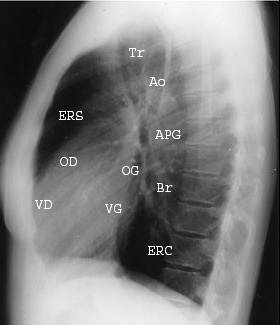

Cliche de profile :

Zylac a divise le médiastin en

trois espace:

• Médiastin moyen (l'espace vasculaire) contient les gros

vaisseaux (les veines caves et leurs tributaires, l'aorte

thoracique ascendante et ses branches).

• Médiastin antérieur (l'espace prévasculaire ) contient des

organes comme le thymus, la thyroïde et les parathyroïdes.

• Médiastin postérieur (l'espace post-vasculaire ) contient

la trachée, l'œsophage, l'aorte thoracique descendante et la

veine azygos.

Une ligne tranversal à travers fene6tre aortique

divisier le mediastin en deux superieure et

inferieure |

Profile droit |

Profile gauche |

trois espace: Anterieure , moyen et posterieure |